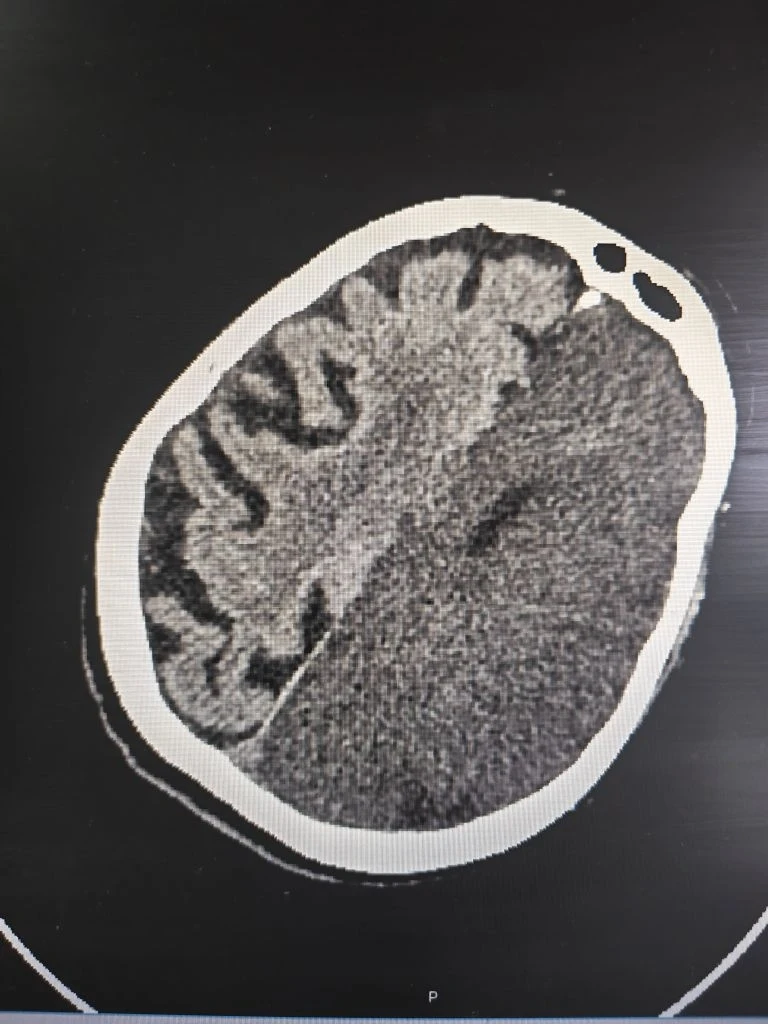

В больницу скорой медицинской помощи №8 Воронежа поступила семидесятишестилетняя женщина в крайне тяжелом состоянии. Накануне вечером она внезапно почувствовала сильную слабость в руке и ноге, но вызывать врачей не стала, решив дождаться утра. Лишь спустя несколько часов, когда самочувствие резко ухудшилось, пациентку наконец доставили на «скорой» в стационар. К тому моменту у нее уже полностью отсутствовали движения в правой половине тела, что говорило о серьезном поражении мозга.

Срочно проведенная компьютерная томография подтвердила самые опасные опасения: у женщины диагностировали обширный ишемический инсульт. Это состояние означает, что из-за острого нарушения кровообращения значительный участок мозга перестал получать кислород, и клетки начали гибнуть. Подобный тип сосудистой катастрофы медики относят к числу наиболее тяжёлых: даже при своевременной помощи прогноз часто остаётся неблагоприятным, а риск летального исхода крайне высок.